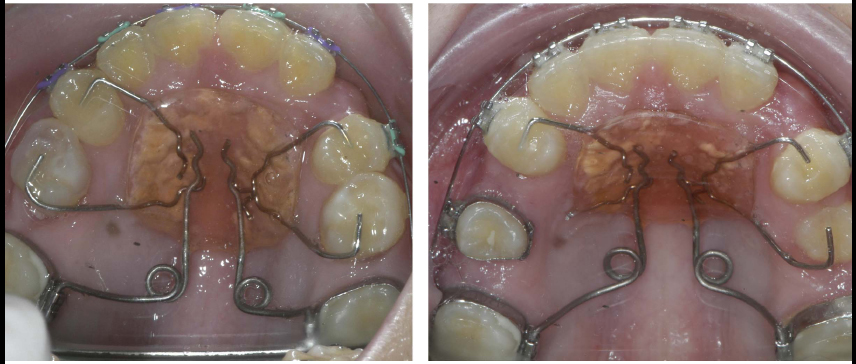

The treatment objectives were to expand the maxillary arch, coordinate arches, eliminate the posterior crossbite, and establish a Class I molar and canine relationship. Treatment was started by bonding metal 0.022-in slot pre-adjusted edgewise appliances with a rapid palatal expander (RPE) to correct the posterior crossbite. Instruction was given to the patient and parents to do one turn per day of the expansion screw for 14 days. The RPE was removed after a five-month retention phase. A pendulum appliance was then delivered to start the distalization process. After eight months, enough space was created for both maxillary canines, and a Class I molar relationship was achieved (Figs. 5 and 6). Detailing was performed using 0.017 x 0.025 titanium molybdenum alloy (TMA) archwire. Upon completion of treatment, maxillary and mandibular Hawley retainers were delivered, and the patient was instructed to wear the retainer for 24 hours per day (Figs. 7 and 8).